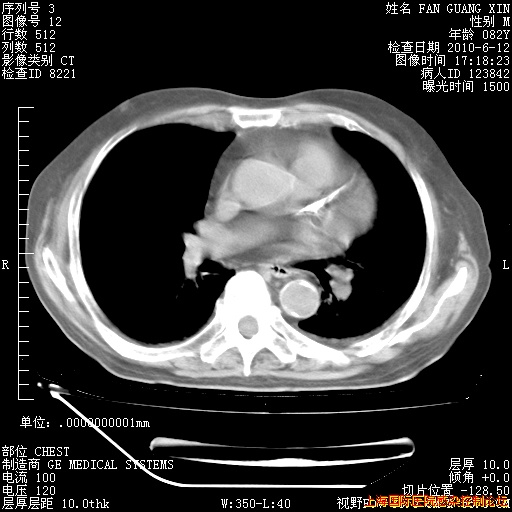

6月12日纵膈窗